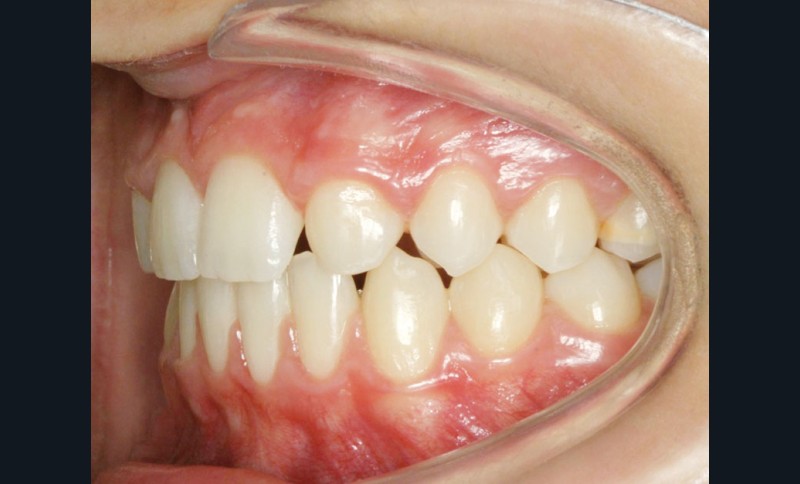

Le traitement orthodontique sans extraction à l’arcade mandibulaire a permis d’établir une occlusion de classe II thérapeutique équilibrée et un sourire harmonieux (fig. 4 et 5).

Une discrète coronoplastie par soustraction a adouci les contours des pointes cuspidiennes canines.